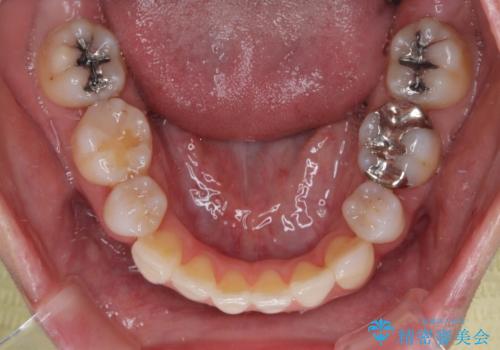

上顎前歯4本は、以前むし歯により神経をすべて取り除かれており、その影響で既に変色を起こしている状態でした。

4本とも歯根部先端の骨が炎症により吸収していることがレントゲン写真から示唆されたため、矯正治療後に4本を再根管治療し、その後上顎6歯をオールセラミッククラウンにて補綴治療することとしました。